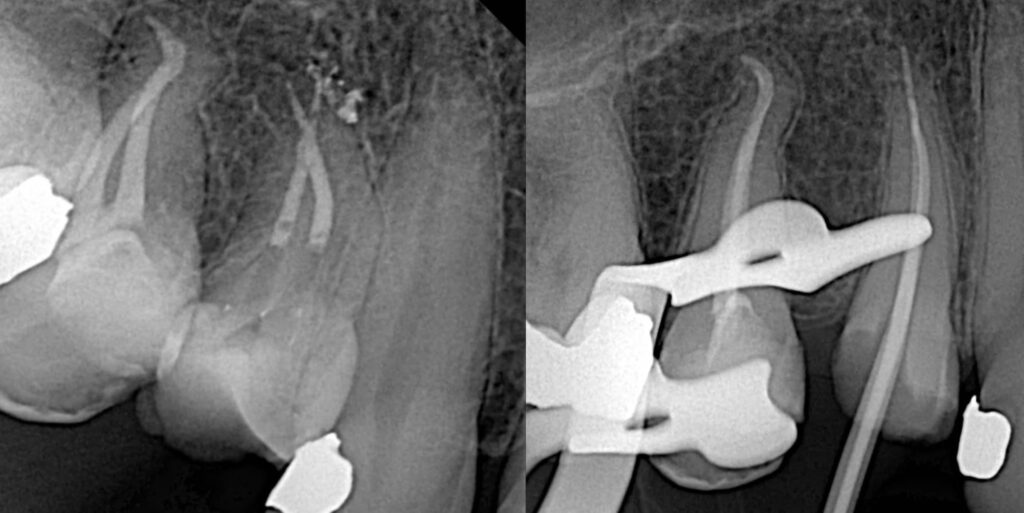

A patient presented with continuous pain localized to the first upper premolar. The pain intensified upon biting and exposure to hot stimuli. Clinical examination and radiographic analysis revealed a severely decayed and structurally compromised tooth with large carious lesions. Percussion testing elicited pain, and the radiograph confirmed pulpal necrosis.

Based on the clinical findings and radiographic evidence, the diagnosis was necrotic pulp of the maxillary first premolar. Root canal treatment (RCT) was planned for the two canals identified in the tooth.

The access cavity was prepared during the first visit. Canal negotiation began with stainless steel K-files (#10, #15, and #20), followed by the use of the SX opener from Rogin to facilitate coronal flaring. Two separate roots and canals were confirmed using an apex locator and radiographs, with canal lengths measuring approximately 19 mm.

Initial manual preparation was completed up to size 20. Final canal shaping was performed using the Rogin Super Flexi Files Kit to size 25/0.04. These files, made from heat-treated Nickel-Titanium CM wire, provided excellent flexibility for safe navigation of the canal curvature, while the square cross-section ensured effective cutting and debris removal with minimal transportation.